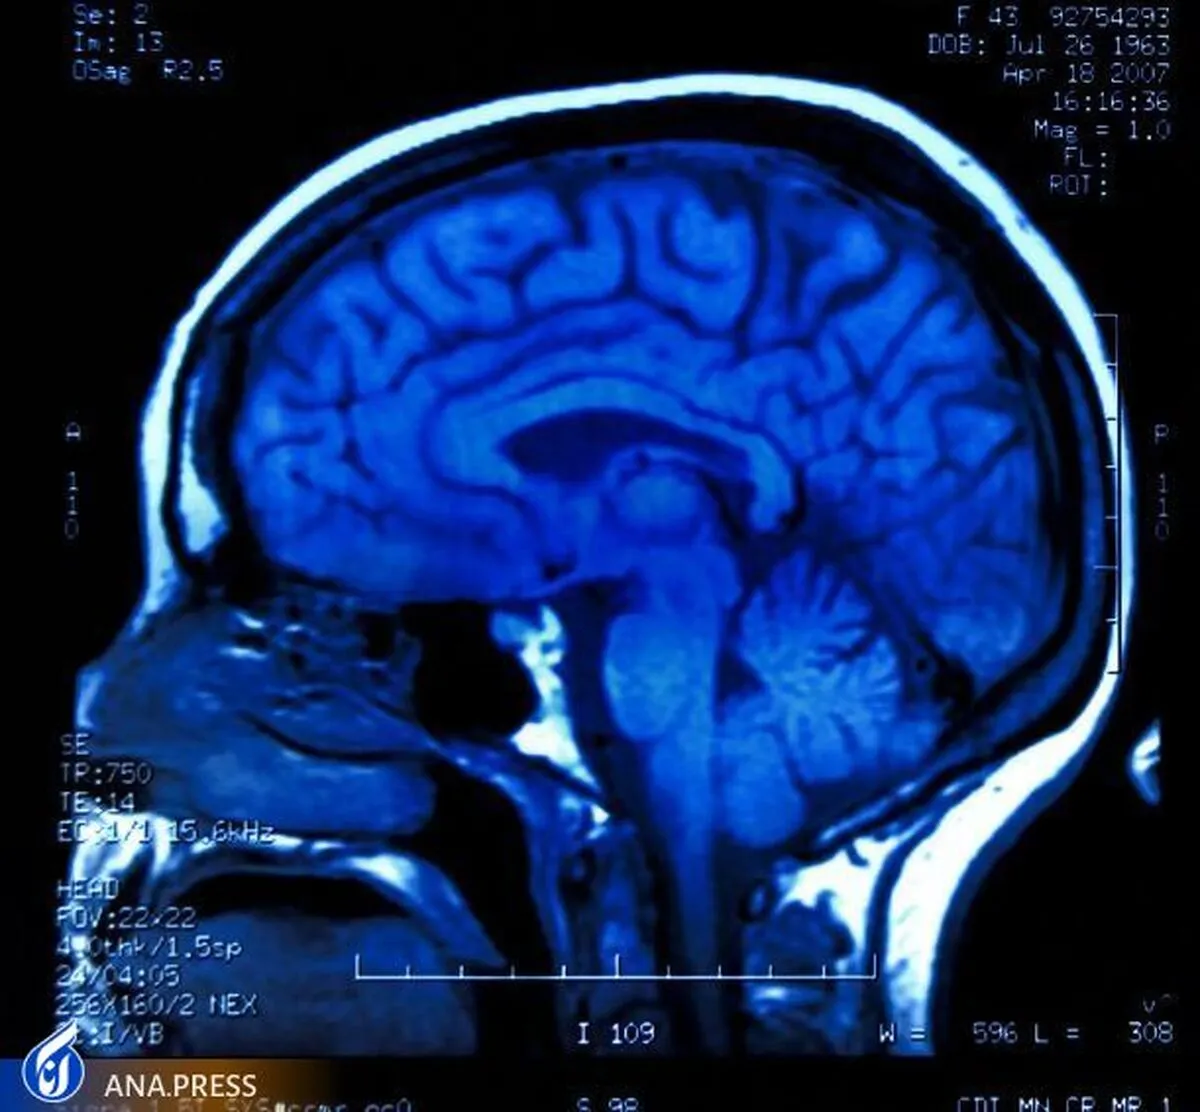

ساختار تشریحی ناشناخته قبلی در مغز کشف شد

به گزارش گروه دانش و فناوری خبرگزاری آنا به نقل از وبگاه (سای تک دیلی)، یک کشف اخیر که در مجله Science گزارش شده است، یک جزء ناشناخته قبلی از آناتومی مغز را توصیف میکند. این جزء جدید هم بهعنوان یک سد محافظ و هم بهعنوان پایهای عمل میکند که از آن سلولهای ایمنی میتوانند از هرگونه نشانهای از عفونت یا التهاب در مغز مراقبت کنند.

یک غشای تازه کشف شده در مغز به نام SLYM یک سد نازک، اما محکم است که به نظر میرسد CSF "تمیز" و "کثیف" را جدا میکند و سلولهای ایمنی را در خود جای میدهد.

لایه جدیدی که توسط تیم تحقیقاتی مستقر در ایالات متحده و دانمارک کشف شد، فضای زیر لایه عنکبوتیه، فضای زیر عنکبوتیه، را به دو بخش تقسیم میکند که توسط لایهای که به تازگی توضیح داده شده است، از هم جدا شده است، که محققان آن را SLYM، مخفف Subarachnoidal LYmphatic- مینامند. مانند ممبران در حالی که بسیاری از تحقیقات در این مقاله عملکرد SLYM را در موشها توصیف میکنند، آنها همچنین حضور واقعی آن را در مغز انسان بالغ نیز گزارش میدهند.

غشای جدید بسیار نازک و ظریف است و تنها از یک یا چند سلول در ضخامت تشکیل شده است. با این حال SLYM یک سد محکم است و فقط به مولکولهای بسیار کوچک اجازه عبور میدهد. به نظر میرسد CSF "تمیز" و "کثیف" را از هم جدا میکند.